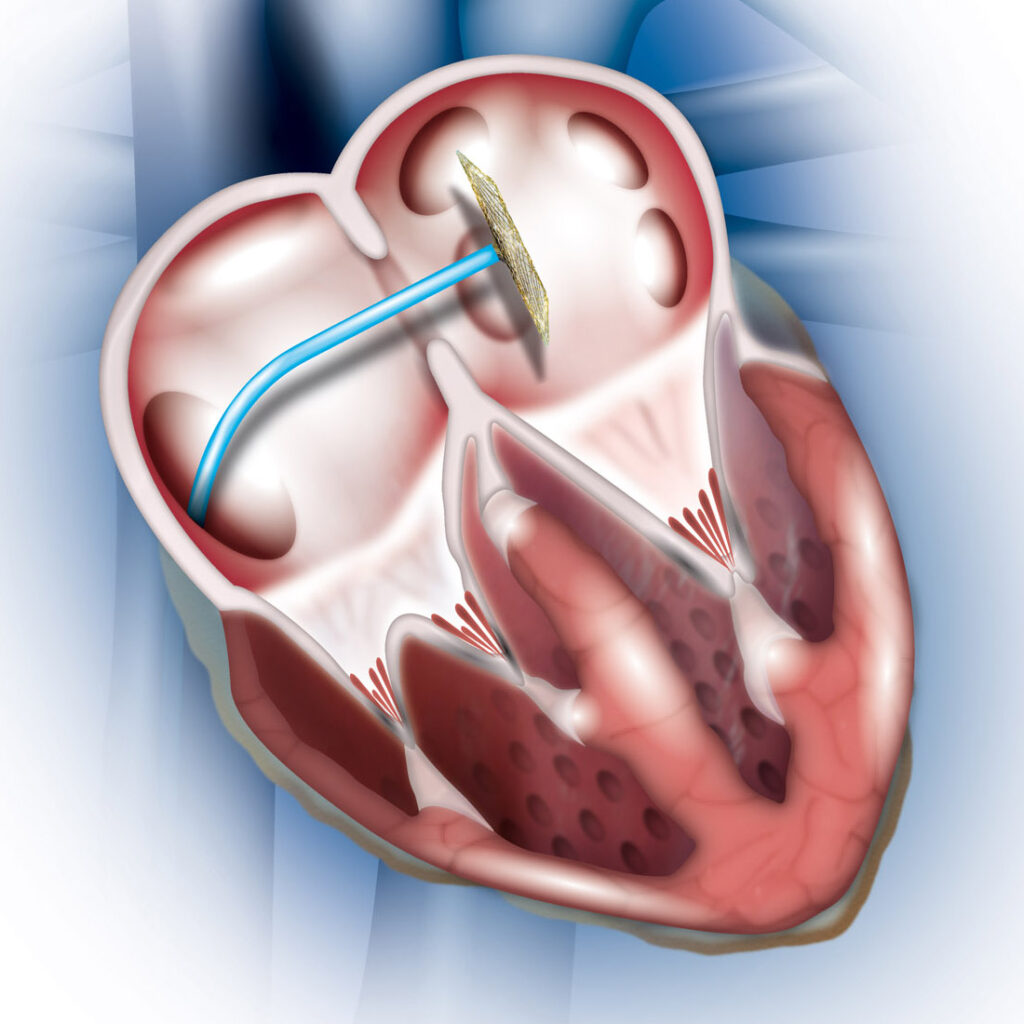

Value added benefits of the ASD Surgical Closure Open Surgery:

Value added benefits of the VSD Surgical Closure Open Surgery:

Value added benefits of the VSD Closure:

Value added benefits of the AVSD Closure:

Value added benefits of the ASD Closure: